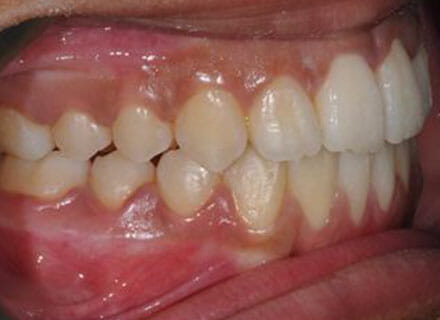

This patient came to us because she hated her smile: it was too narrow, the upper front teeth were all crowded into each other and twisted. She couldn’t eat a sandwich properly with the front teeth because of the gap – the open bite. We were able to expand both jaws to make space to align all the teeth without having to extract – in about 18 months using clear brackets.